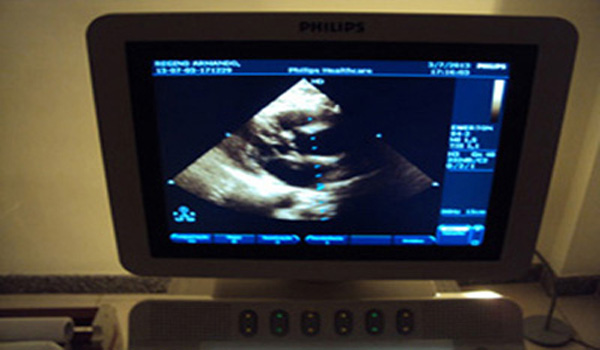

Proporcionar novas formas de tratamentos cardiovasculares, utilizando tecnologia e profissionais de alto nível. Esse é o objetivo do Prontocor.

Dentre os procedimentos desenvolvidos, está o Fechamento Percutâneo da Auriculeta Esquerda,... [Leia Mais]